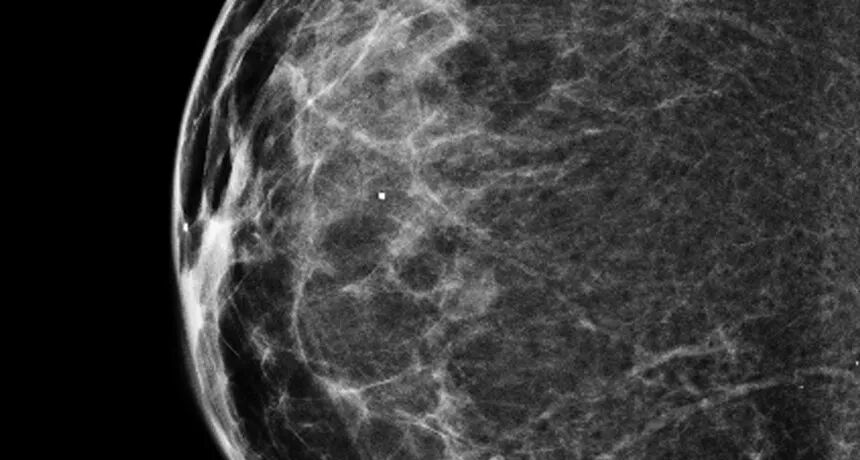

除了彩超三维,乳腺三维近年来发展态势迅猛,广受推崇,那么乳腺三维是否真的优于乳腺二维呢?

部分乳房护理中心认为最新的三维乳腺摄影技术的诊断准确性更高。最初的科研测试表明,三维乳腺摄影技术确实在诊断的敏感性上更优,而实际的临床数据也说明,采用三维比二维成像对于减少乳腺癌的死亡人数效果明显。

而三维乳腺摄影技术是从乳房周围的各个角度拍摄图像,然后将这些乳香组合成三维成像;而标准的二维乳腺成像技术通常从两个角度拍摄图像,最终提供的是乳房的平面图像。因此,使用三维乳腺摄影技术,放射科医生同时获得了三维和二维图像。